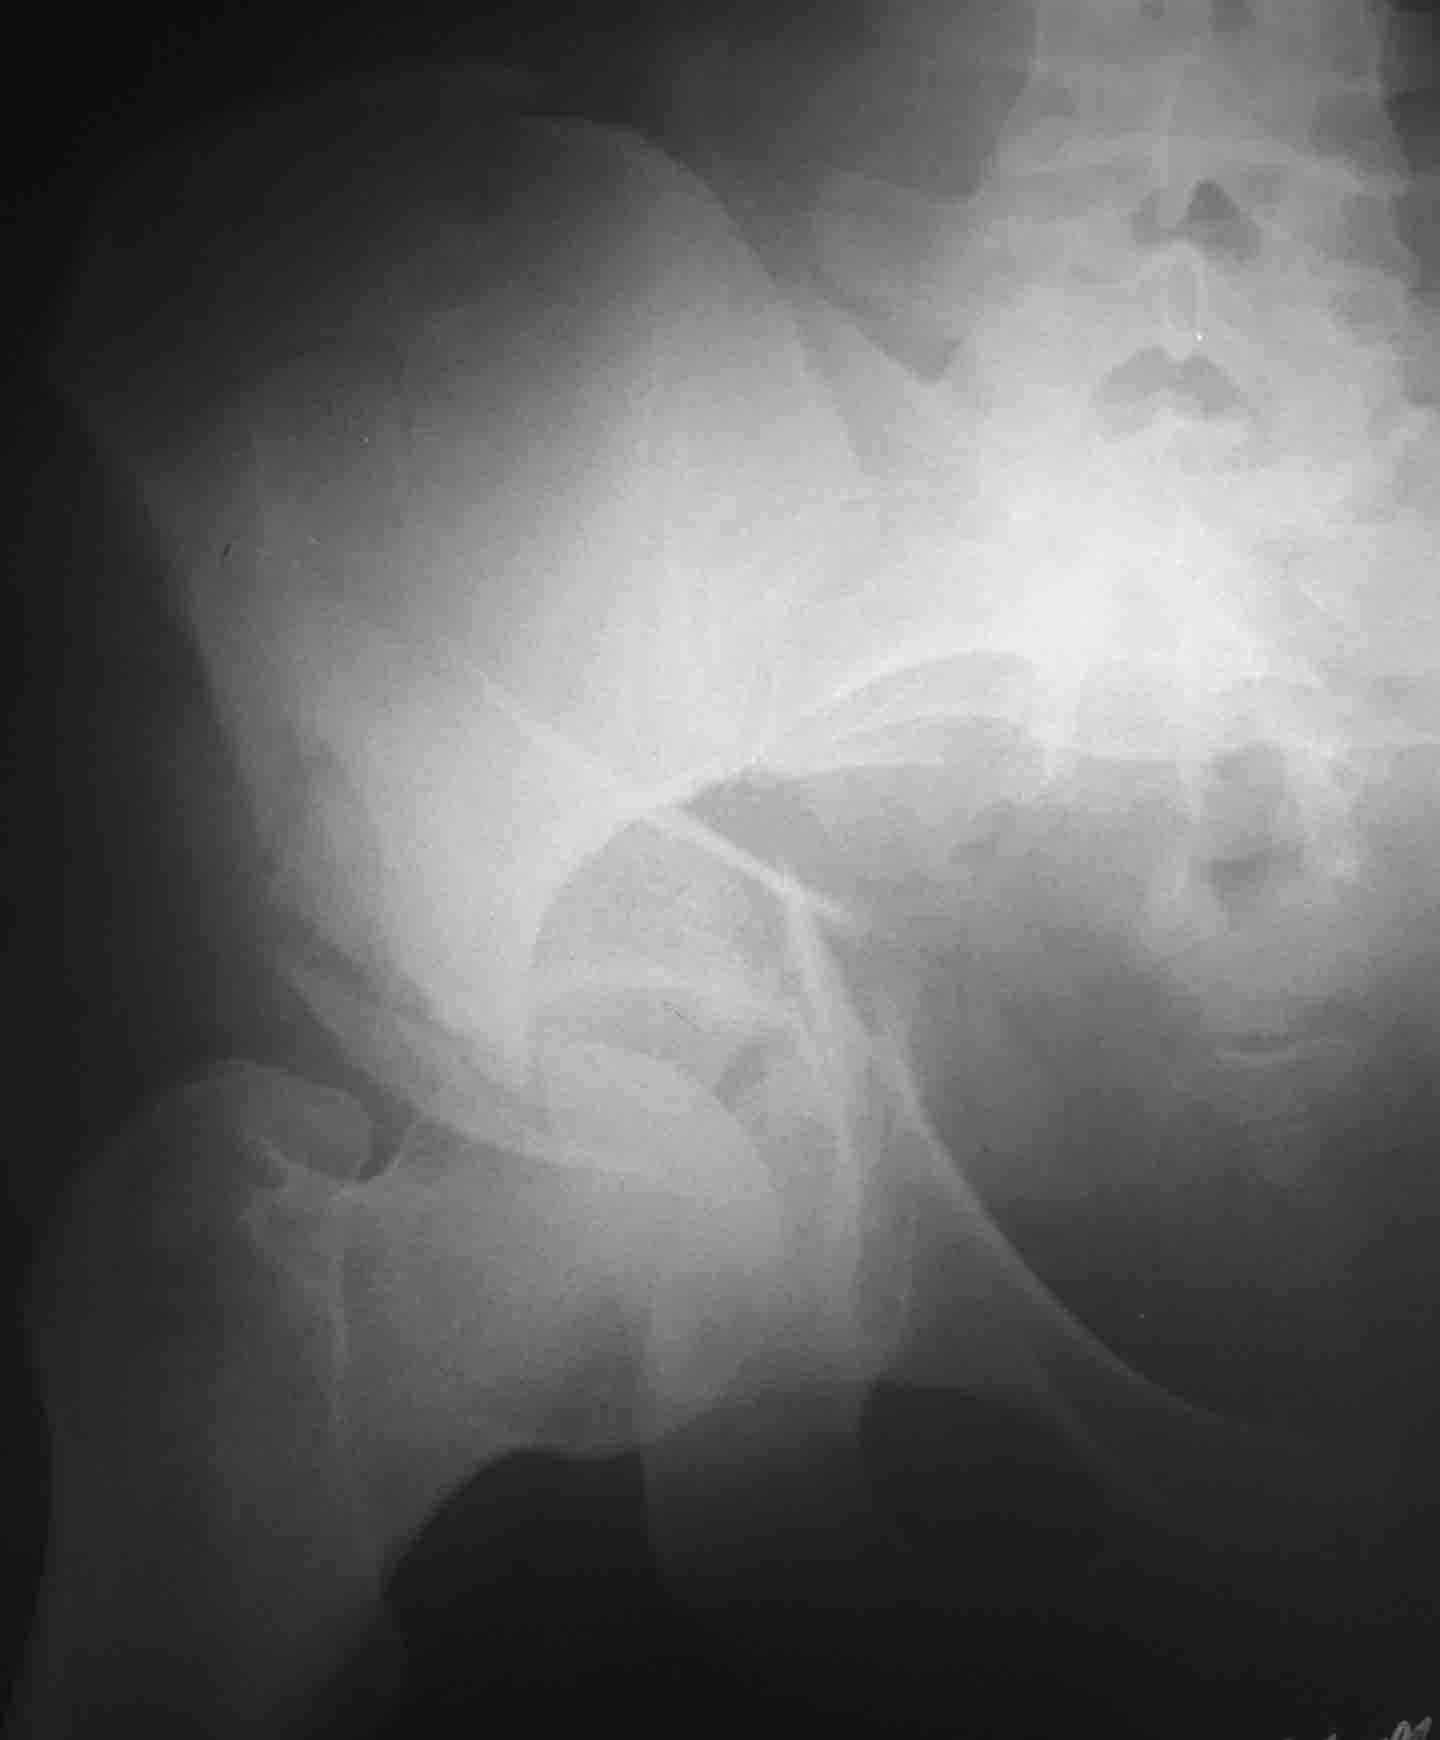

Пациентка 26 лет поступила в больницу 9 дней назад после кататравмы (падение с 4-го этажа) Тяжелая сочетанная травма: Ушиб головного мозга средней тяжести.З/полифокальный перелом таза (оскольчатый чрезвертлужный справа, латеральной массы крестца слева со смещением отломков. З/оскольчатый перелом н/3 правого бедра. З/оскольчатый перелом правой пяточной кости. Тупая травма живота - разрыв слизистой толст кишечника, кисты яичника.

При поступлении - лапаротомия, ушивание ран кишечника, резекция кисты; скелетное вытяжение за правую н/конечность (бугрист б/б кости) На 2-й день на таз наложен стержневой аппарат из "того что было" (по паре стержней в подвздош кости) - естественно, при таком переломе фиксации таким аппартом практически никакой. Пациентка 2 дня назад переведена из реанимации в травм отделение, состояние средней тяжести, показатели красной крови - эритр 2,7; Гб - 75 г/л; Спицевое вытяжение за б/вертел не накладывали из-за возможности инфицирования бедра (пациенка по комплекции довольно упитанная) Встает вопрос - что и в какой последовательности делать с поврежденными сегментами скелета? Думали о варианте: Первым этапом - погружной остеосинтез бедра (DCS? интерлокинг?)и ,возможно, пяточной кости.Вторым этапом - стержневой остеосинтез таза с бедренным модулем (внутренний остеосинтез таза, думаю, по соматике пациентки будет возможен не скоро)